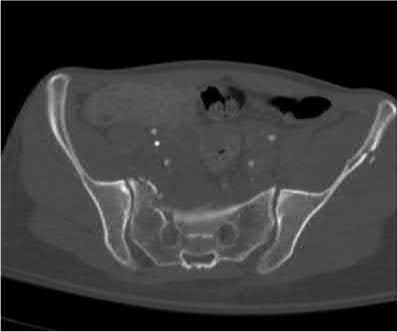

Which of the following images shows an injury pattern most consistent with a lateral compression type 3 pelvic ring injury?

Figure C is an axial CT scan of a lateral compression type 3 (LC3) pelvic ring injury.

Classically, LC3 injuries demonstrate an ipsilateral lateral compression and a contralateral APC (windswept pelvis) fracture pattern. The most common mechanism of injury in these cases is a rollover MVC or pedestrian vs. auto. LC1 injuries are characterized by an oblique or transverse ramus fracture and ipsilateral anterior sacral ala compression fracture, while LC2 injuries consist of a rami fracture and ipsilateral posterior ilium fracture dislocation (crescent fracture). While LC1 injuries can often initially be managed conservatively with protected weight-bearing and close observation, LC2 and LC3 pelvic ring injuries are almost universally operative.

Answer 1: This represents a lateral compression type 2 injury. Answer 2: This represents a lateral compression type 1 injury.

Answer 4: This represents an anterior posterior compression type 2 injury. Answer 5: This represents an anterior posterior compression type 3 injury.